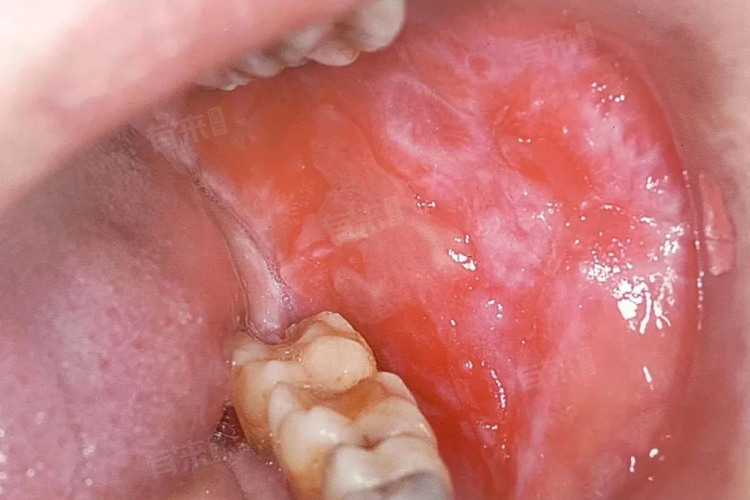

- 局部治疗是口腔扁平苔藓的主要手段之一,医生会根据病损情况选用药物。对于糜烂型病损,常用糖皮质激素制剂局部涂抹,以减轻炎症、促进创面愈合;非糜烂型病损可遵医嘱使用维A酸类药物,调节上皮细胞代谢,改善病损状态。此外,含漱液(如氯己定含漱液)可保持口腔清洁,减少继发感染。

治疗效果存在个体差异,部分患者经治疗后症状可完全缓解,病情长期稳定;但也有患者因病情复杂、诱因持续存在(如未控制的糖尿病、长期精神紧张),导致病情反复。需要注意的是,少数口腔扁平苔藓存在恶变可能,尤其是长期不愈的糜烂型病损,因此治疗期间需定期复查,监测病损变化。